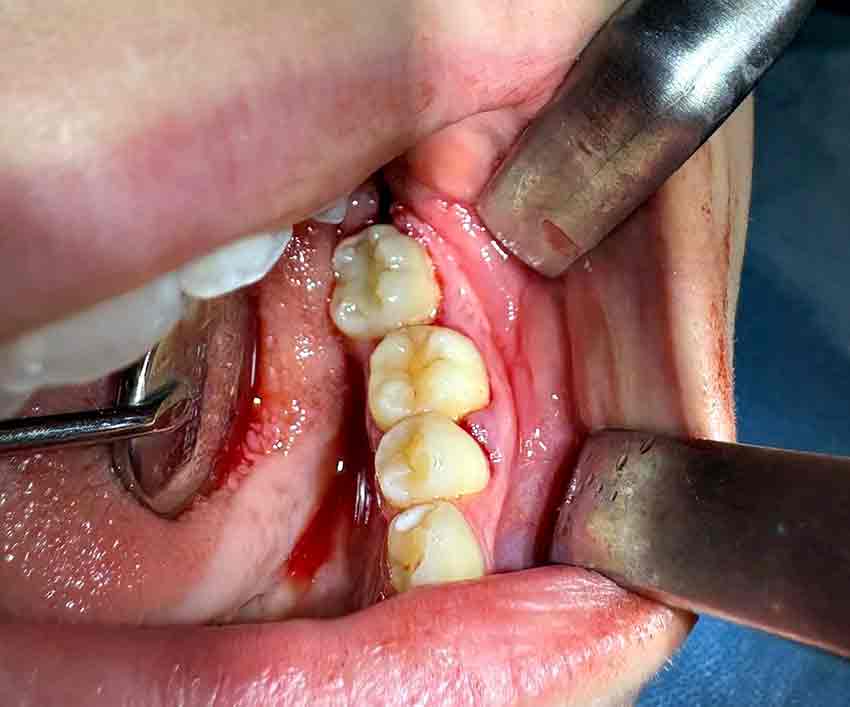

Hastaneden yapılan açıklamada operasyonun detayları şu şekilde paylaşıldı. Genç bir hastanın tüm tedavi uygulamalarına rağmen kurtarılamayan daimi azı dişi, tedavi amacıyla çekildi. Ancak çocuk yaşta çene gelişimi devam ettiği için implant uygulaması gibi klasik tedavi yöntemleri uygun görülmedi. Bu nedenle hastanın kendi ağzında, kemik içinde gömülü halde bulunan üçüncü azı dişi (yirmi yaş dişi), operasyon mikroskobu eşliğinde cerrahi olarak çıkarıldı ve hazırlanan çekim yuvasına nakledildi. Ayrıca dişin daha sağlıklı bir şekilde iyileşebilmesi için hastanın kendi kanından elde edilen PRF (Platelet Rich Fibrin) biyomateryali, nakil işlemi öncesinde hazırlanan yuvaya yerleştirildi.”

Bu özel işlem, hastanın kendi dişi kullanıldığı için doğal görünüm ve fonksiyon açısından büyük avantaj sağlarken, vücut tarafından kabul edilme olasılığını da artırıyor. Uzun vadeli başarı oranlarının oldukça yüksek olduğuna dikkat çekildi.